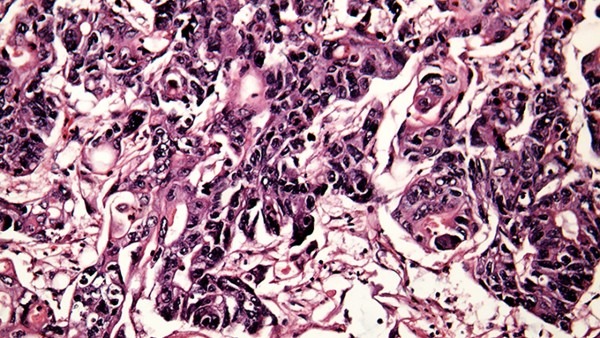

潜伏期过后患者身体开始出现出现明显病症,长出淡红色或污红色的小丘疹,如果没有及时治疗的话,这些小疙瘩可很快长大,发展为乳头状、菜花状、鸡冠状等形状的疣体赘生物,表面呈颗粒状,或呈现湿润或有出血的情况,这些疣体赘生物可很快破溃,形成溃疡面。